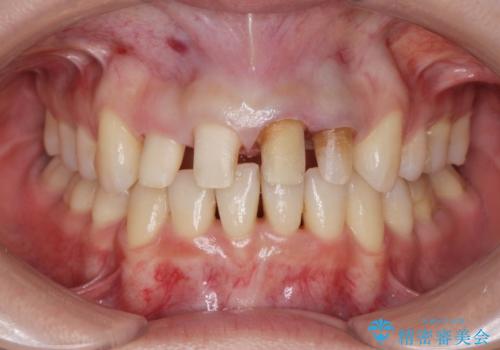

- 神経の死んでしまっている前歯の変色の改善を求めて来院されました。

根管治療をしたのち時間が経過して変色が目立つ歯と、レジン充填が複数箇所に及んでいる歯も同時にオールセラミック治療を行っていくこととなりました。

- 52.8万円(ジルコニアクラウン×4・仮歯×4)費用は治療当時の料金となります